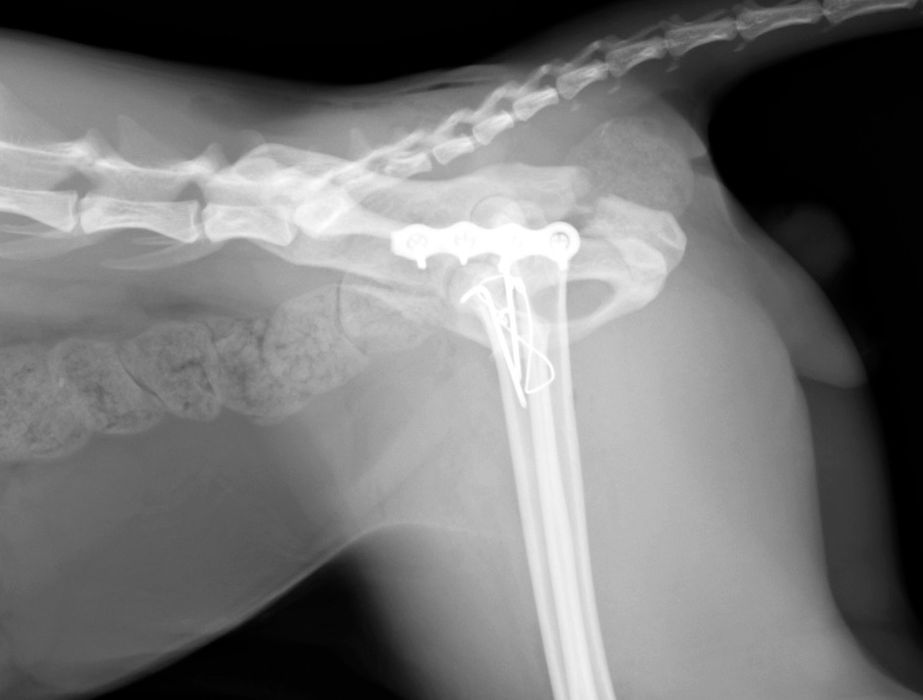

骨折治療について

動物も人間と同じように骨折や脱臼をします。

原因として交通事故などの大きな外力によるものもありますが、日本では小型犬が主体となっているため、ソファや抱っこしている所からの落下といった比較的小さな外力でも生じることが多くなっています。

骨折や脱臼の治療は、ギプスなどの処置のみで済むケースもありますが、ほとんどのケースは完全骨折や脱臼を生じますので、手術が必要となります。

当院における骨折治療は、動物のステータス、骨折の発生部位や分類などを考慮して「髄内ピン」「骨プレート」「創外固定器」を単独もしくは組み合わせて使用することで適当な固定力を得られるように施術しています。

●骨プレート

ステンレス製もしくはチタン製の金属の板(プレート)と骨ネジ(スクリュー)を使用して固定を行います。

●髄内ピンと骨プレートの併用(プレート-ロッド併用法)